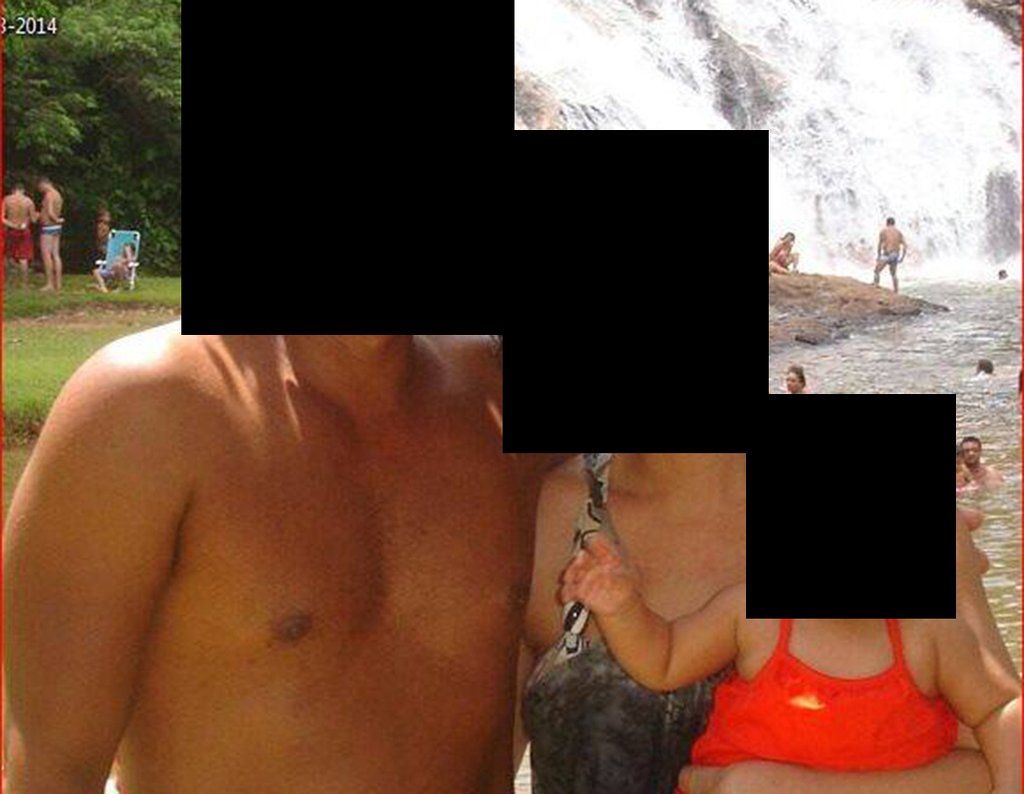

- Doze anos e três meses pós-operatório: Paciente exibiu uma vida sem limitações significativas, superando o déficit funcional e exercendo atividades diárias com desenvoltura.

O tratamento do condrossarcoma na paciente de 19 anos envolveu uma abordagem cirúrgica meticulosa com pelvectomia interna total. O acompanhamento a longo prazo demonstrou uma excelente recuperação funcional e ausência de recidiva, ressaltando a eficácia da ressecção cirúrgica com margens de segurança. A paciente alcançou uma qualidade de vida plena, participando ativamente de atividades sociais e pessoais.

A paciente exibe, com alegria, sua vida sem limitações significativas. Mostra a total superação do déficit funcional, exercendo atividades da vida diária com desenvoltura, figuras 81 a 90.

Vídeo 1: Marcha com apoio total no membro operado, carga monopodal com bom equilíbrio, boa função de flexão dos quadris e joelhos com carga. Excelente resultado funcional para uma hemipelvectomia interna total, sem reconstrução, após 12 anos e três meses da cirurgia.